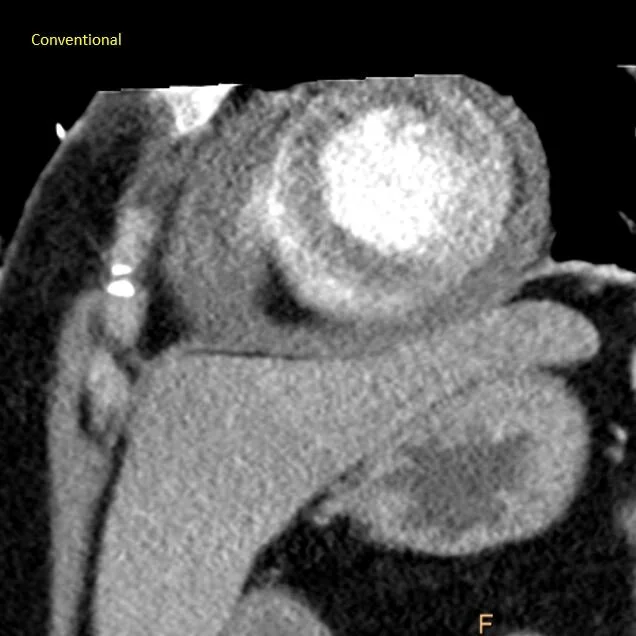

The next day she had abdominal pain and a CT scan of the abdomen and pelvis was performed. There was no acute finding in the abdomen, but the cuts through the lower chest showed interesting findings in the LV. On 40 keV monoE and iodine map, there is a large perfusion defect in the LV corresponding to the LAD territory. This is better seen on short-axis view. On spectral CT, this is a slam dunk, while on routine CT it would be quite a stretch to make this call.

Conventional CT: short axis. You might call the perfusion defect, if you were lucky and having a good day.